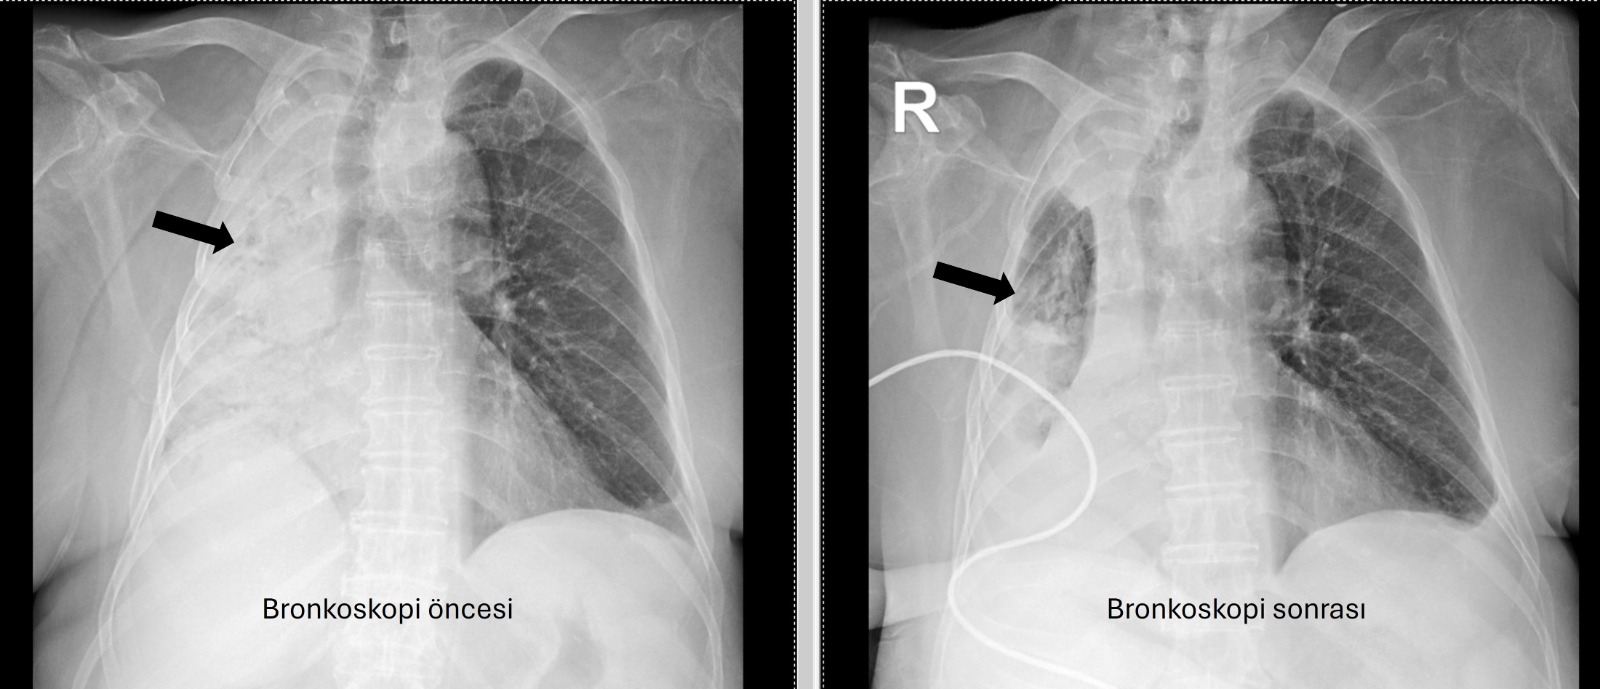

Önceki tetkiklerinden, sağ akciğere giden hava yolunun bütünüyle kapalı olduğu görülen hastaya acil bronkoskopi planlanıp hemen işlemin gerçekleştirildiğini söyleyen Prof. Dr. Altınışık Ergur, hastanın tıbbi öyküsünde hava yoluna yabancı bir cisim kaçma kuşkusu, ardından öksürük, morarma ve ani nefes darlığı gibi bir durum olmadığını ve bu nedenle sorunun ne olduğunun anlaşılması gerektiğini belirten Prof. Dr. Altınışık Ergur sözlerine şöyle devam etti: “Fleksibl (esnek, eğilip bükülebilir) bronkoskop ile hava yolları incelenirken çok yoğun ve koyu sekresyon olduğu, bunun iyice temizlenmesi sonucunda ancak hava yollarının incelenebileceği görüldü. Aspiratör (içerideki salgıları emmeye yarayan bir cihaz) sayesinde hava yollarına steril sıvı verilip emilerek bu temizlik yapıldı. Sonrasında sağ akciğere giden hava yolunda sarı bir nesne olduğu görüldü. Bu hâliyle yabancı cisim olduğu anlaşıldığı gibi bunun mısır tanesine benzerliği de açıktı. Yabancı cismi çıkarma işlemi genel anestezi altında, rijit bronkoskop ile yapılmak üzere planlanabilirdi; çünkü bu durumun tedavisi yabancı cismin oradan, ek sorun oluşturmaksızın çıkarmaktı. Ancak, genel anestezi altındaki bir işlem için hastanın genel durumu bozuk olduğundan, özellikle ek hastalıkları ve enfeksiyon varlığı ile işlem riski artacağından hastadaki cismin fark edildiği sırada çıkarılmasına şans vermek daha uygun görüldü. Hava yolu içindeki sıvıları emen aspiratörün gücünü kullanılarak cismin çıkarılması mümkündü. Bronkoskobun ucu, sarı cismin gövdesine dayanıp aspiratör ile emme sayesinde ikisi birbirine sımsıkı yapıştırıldı. Emme gücünün azaltılmamasına dikkat ederek yabancı cisim ve bronkoskop, aynı zamanda hava yollarından dışarıya başarı ile çıkarıldı. İşlem sonrasında hasta yakınına mısır tanesi açısından tıbbi öykü yeniden sorulduğunda, hastamızın bundan beş ay önce yediği pizzanın üzerinde mısır taneleri olduğu öğrenildi. O sırada ani bir yakınma ortaya çıkmadığı için böyle bir olasılık akla gelmemişti. Düşkün hastalar taneli gıdalar yerken, bu durumun fark edilmeden de gelişebileceğini göstermesi açısından önemli olan bu tablo, hastaların bir dedektif titizliği ile değerlendirilmesi gerekliliğini bir kez daha ortaya koymaktadır.” şeklinde konuştu.